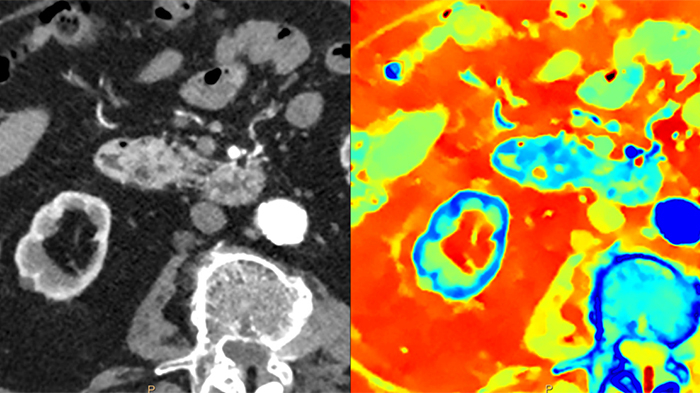

Le scanner à détection spectrale a transformé la TDM classique en TDM quantitative. Le système Philips Spectral CT 7500 de deuxième génération reçoit le prix Aunt Minnie du meilleur nouvel appareil de radiologie en 2021.

Contrairement aux images TDM, les images de scanner à détection spectrale collectent 100 % du temps des informations spectrales, sans qu’aucune configuration ou programmation particulière ne soit nécessaire. Ainsi, vous pouvez analyser les données spectrales rétrospectivement pour chaque image à l’aide de différents outils d’affichage spectral. Il est alors possible notamment de régler le niveau mono-énergétique ou d’obtenir.

La TDM spectrale m’aide à différencier objectivement les prises de contraste des hémorragies, évitant ainsi d’effectuer une acquisition de suivi supplémentaire et de garder le patient en observation prolongée. Cela permet une réduction des coûts et des expositions aux rayons pour les patients1,2.